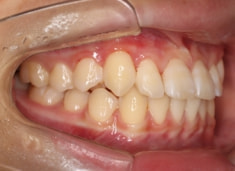

治療前

治療開始時

検査時のレントゲン分析では、上下顎の関係は、上顎の劣成長があり下顎前突傾向という値がでておりましたが、前歯ジャンプ後はフェイスマスクの効果もあり、上下顎の関係は正常化しています。

上顎が若干優位になっていますので、今後の下顎の成長のための貯金になっているくらいです。